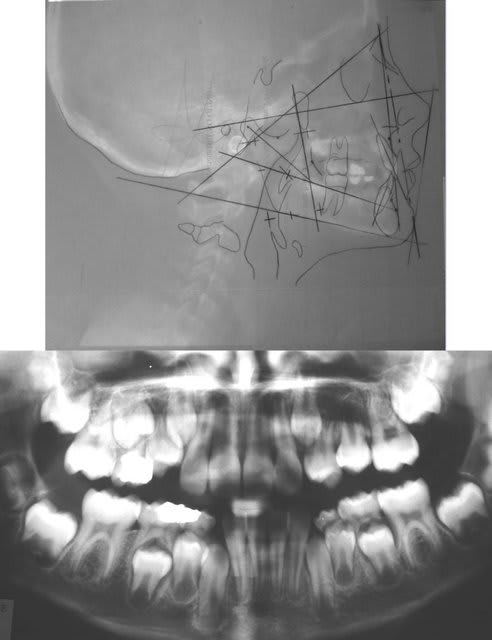

Je serais tout de même assez curieux de jeter un oeil à la cephalo de ce cas, si tu as...

Bon, je vais aller photographier les Rx. Pour jpr.

Rx.

09/07/2006 à 13h40

Grand merci pour les radios Bjc...

Et mille excuses pour cette réponse tardive et pour mon erreur de diagnostic. Ca m'apprendra: je me suis fié à des apparences trompeuses, car il s'agit bien d'une cl.I squelettique , avec mésioposition des secteurs latéraux. Comme quoi, avoir toutes les données du problème, ça peut aider..